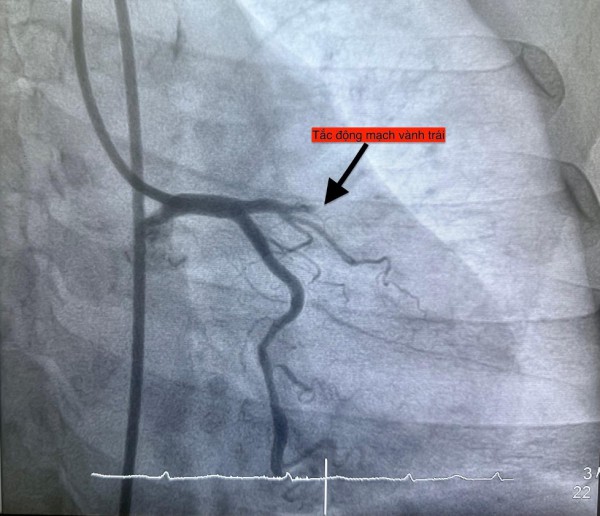

Trường hợp thứ tư, lúc 22 giờ 6 phút, nữ bệnh nhân 61 tuổi nhập viện vì đau ngực, vã mồ hôi; bệnh nhân có đái tháo đường type 2. Điện tim cho thấy nhồi máu cơ tim cấp thành trước.

Hình ảnh chụp mạch vành cho thấy các bệnh nhân bị tắc mạch máu tim (do mảng xơ vữa, huyết khối) dẫn đến tình trạng thiếu máu cục bộ và nhồi máu cơ tim cấp

ẢNH: BV